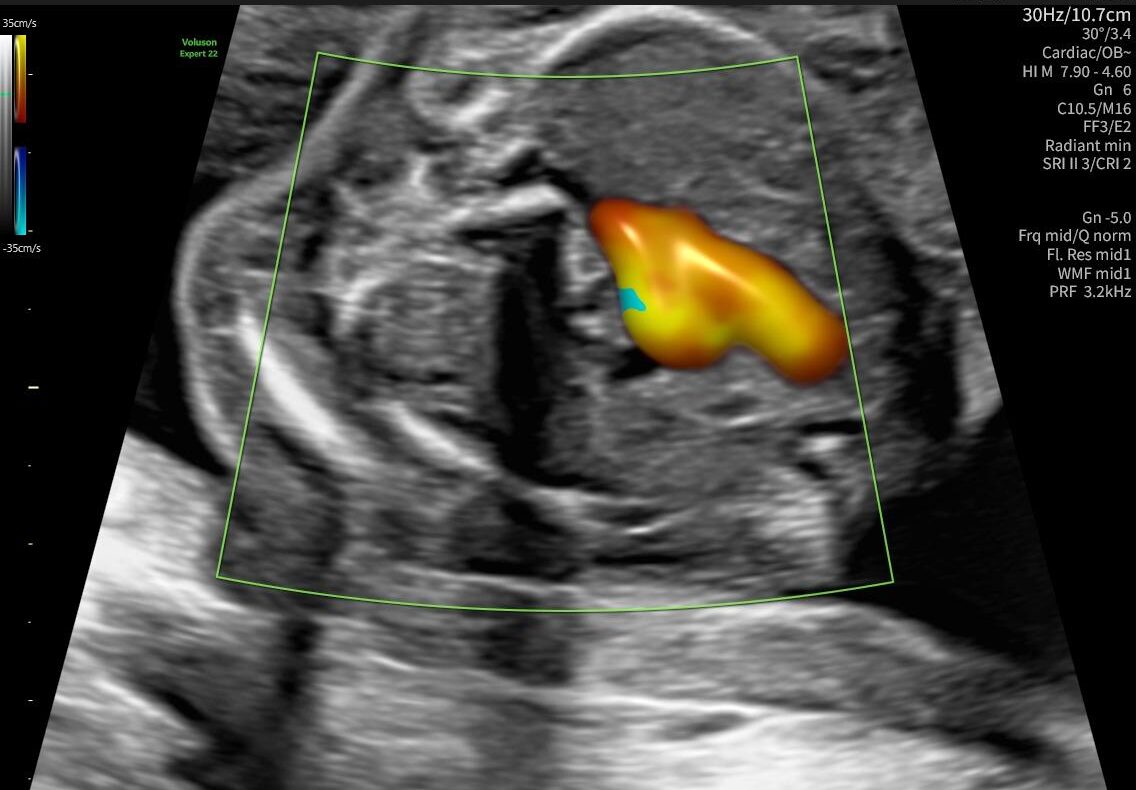

La ecocardiografía fetal es un estudio ecográfico avanzado que permite analizar con detalle la estructura y el funcionamiento del corazón del bebé antes de nacer. Este examen ayuda a identificar posibles alteraciones cardíacas y a evaluar el desarrollo adecuado del sistema cardiovascular fetal.

A través de imágenes ecográficas de alta precisión, los especialistas pueden observar las cavidades del corazón, las válvulas y el flujo sanguíneo, lo que permite realizar un diagnóstico prenatal más completo.